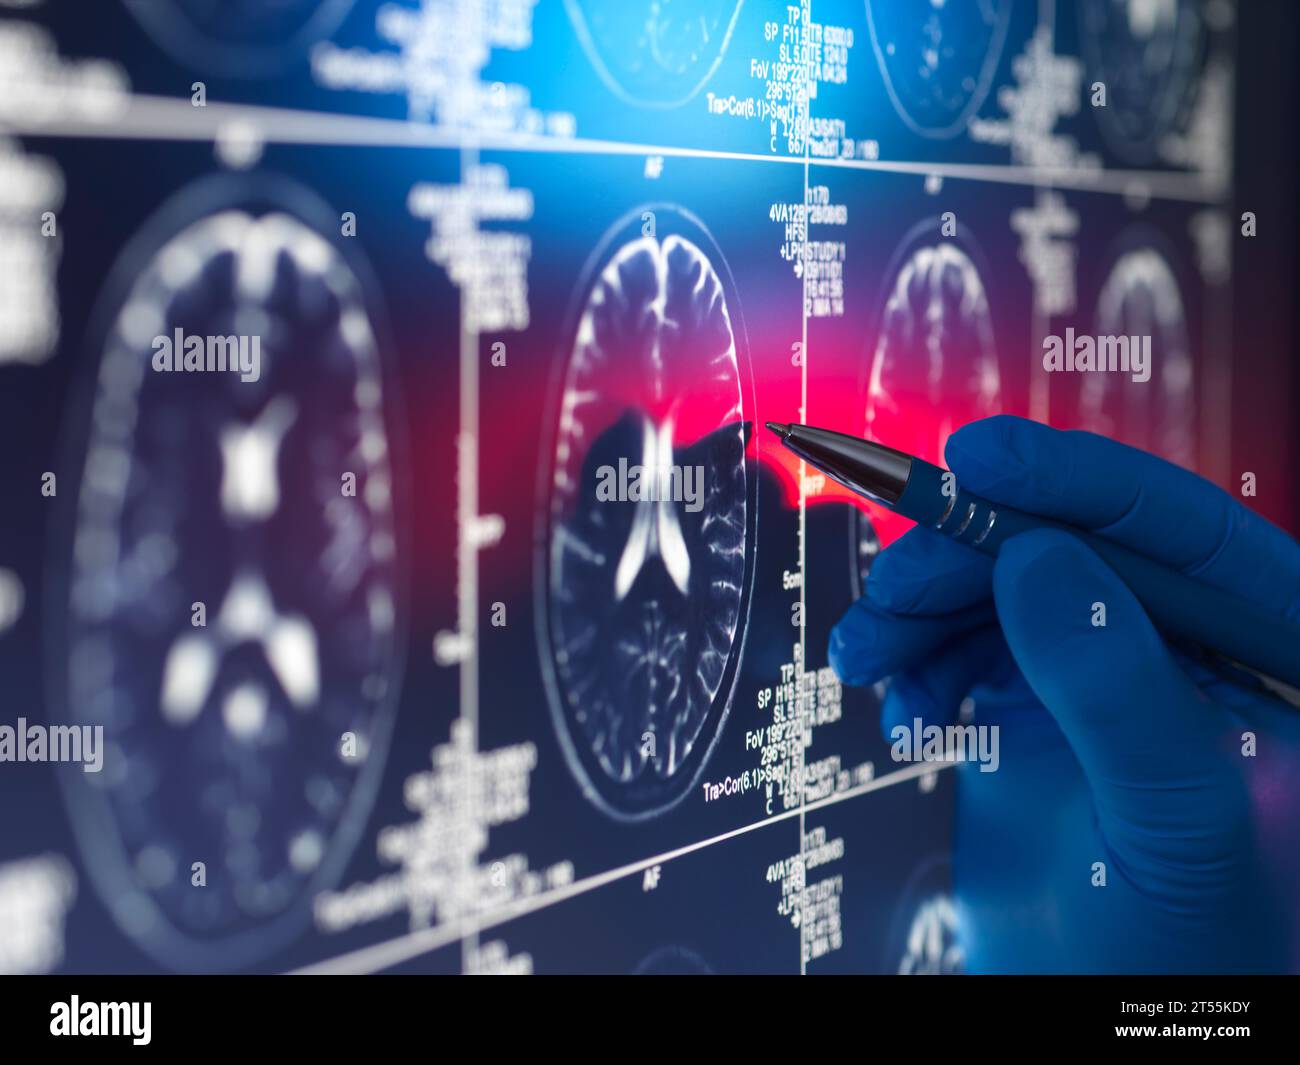

Doctor viewing a patients brain scan on screen Stock Photohttps://www.alamy.com/image-license-details/?v=1https://www.alamy.com/doctor-viewing-a-patients-brain-scan-on-screen-image571140471.html

Doctor viewing a patients brain scan on screen Stock Photohttps://www.alamy.com/image-license-details/?v=1https://www.alamy.com/doctor-viewing-a-patients-brain-scan-on-screen-image571140471.htmlRF2T55KDY–Doctor viewing a patients brain scan on screen